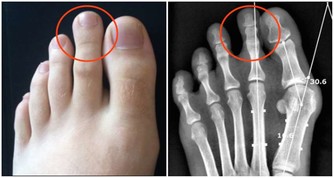

(5)內外八字

走路時,能走正的人其實很少,其中,內八字比較少見,多數人都是外八字。

外八字的成因與走路習慣有關,即移步時須左右移動重心,故而腳尖習慣向左右外撇。這樣的走姿,既不舒服也不雅觀。

正確方法是,行走時找到地上的一條直線(地磚或水泥縫),一腳先對好,腳尖腳跟對齊直線,另一腳與之保持平行,然後照此方向行走,慢慢就可以糾正錯誤的姿勢了。